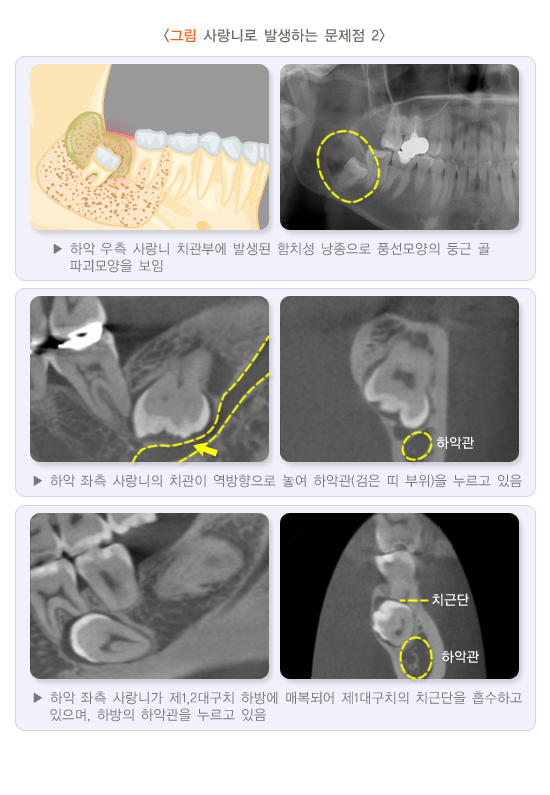

사랑니 주변의 염증이 반복되면 얼굴과 목이 부을 정도로 심해질 수 있으므로 사랑니 주변의 통증이 있다면 염증 치료와 더불어 발치하는 것이 좋습니다. 매복된 사랑니로 인해 흔히 물주머니 또는 물혹이라고 하는 함치성 낭종이 생겨 주변 턱뼈가 파괴되고, 더욱 진행되면 주변 어금니로 확산되어 치아의 생존력이 없어질 수 있습니다.

물주머니가 커지면 작은 충격에도 턱뼈가 부러질 수 있으므로 신속하게 치료해야 합니다. 뼈 속에 아주 깊이 박힌 사랑니는 뽑은 후 신경손상 등의 문제가 발생할 가능성이 높으면 그대로 둘 수도 있습니다. 사랑니를 뽑을 것인가에 대해서는 치과의사와의 상담이 필요합니다.

(2) 하악관 근접

대부분의 사랑니는 치근과 하악관이 매우 근접해 있습니다. 하악관은 하치조 신경이라는 감각신경이 지나는 아래 턱뼈 속의 통로로 사랑니 발치 시 일시적인 신경손상이 발생할 수 있습니다. 감각신경이 손상되면 아래 입술과 아래턱 주변에 감각이 저하되거나 마취된 듯한 느낌이 지속될 수 있습니다. 이러한 부작용은 흔하지는 않지만, 일단 발생하면 오랜 기간 지속될 수 있으므로 담당 치과의사의 진찰 후 정밀한 상담이 필요합니다.